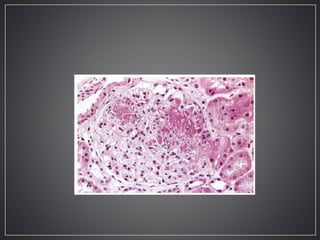

• Biopsy – mononuclear inflammatory cell infiltrate

• Distinctive pattern – perifascicular atrophy

• Segmental fiber necrosis and regeneration

C5b-9 in capillary vessels